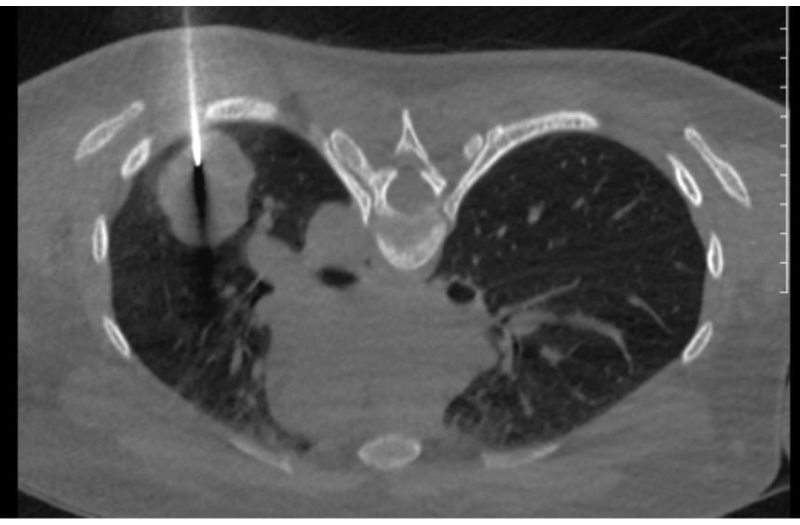

Hình ảnh sinh thiết u phổi trái của Bệnh nhân

Hình ảnh chụp phổi trái: Nhu mô thùy dưới phổi trái có khối mờ kích thước 34x42mm, bờ đều, sau sinh thiết, hiện không thấy tràn khí màng phổi.